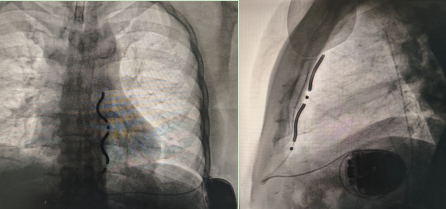

手术中,团队经剑突下及左侧腋中线切口,精准分离腹直肌鞘与膈肌薄弱点,将除颤线圈精确置入胸骨后左缘、心包膜前缘,电极经皮下隧道连接至左侧腋中线 ICD 装置。术中诱颤测试显示,30J 能量一次除颤成功转复,程控测定 R 波振幅达 5.3mV,各项参数均符合标准。据了解,该病例是目前国内已知胸骨最短的 EV-ICD 植入患者,手术难度极具挑战性。

同日下午,红角洲院区陈琦教授团队为一名确诊罕见"法布雷病"的晕厥患者成功实施第二例手术。该患者为心源性猝死高危人群,术中设备感知功能良好,3 倍感知灵敏度达 0.45mV,室颤识别准确,30J 除颤一次成功转复。